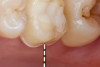

Figure 1 through Figure 14 illustrate steps involved in the fabrication of zirconia restorations using CEREC. Figure 15 through Figure 21 show preparations and postoperative results in two case examples of patients who received zirconia indirect restorations.